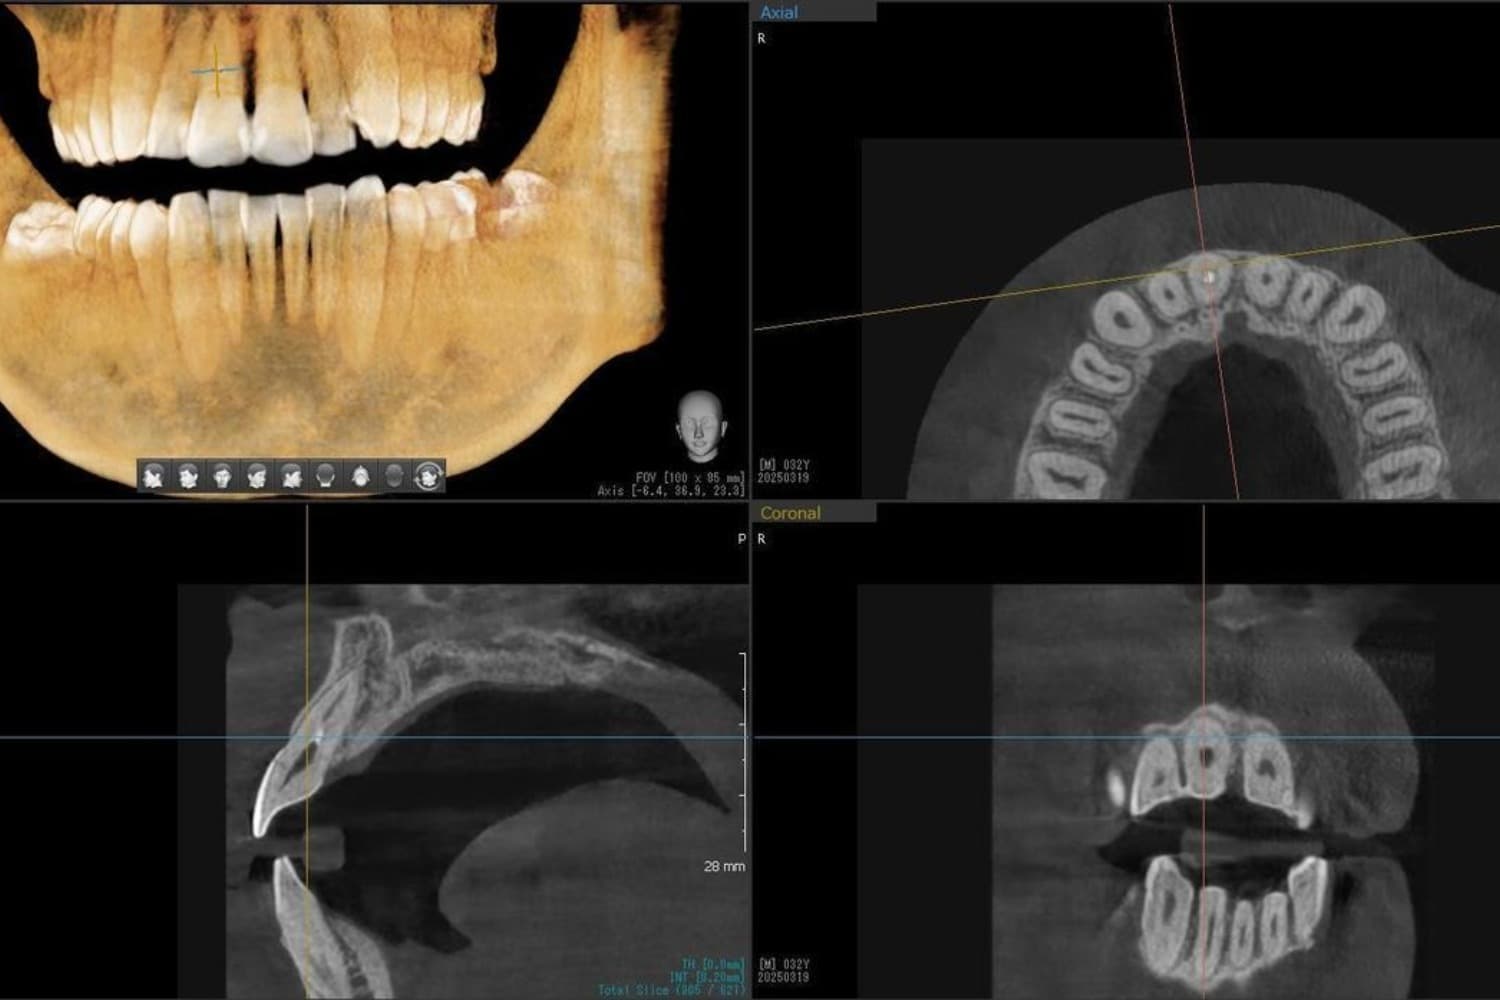

歯根破折した前歯のインプラント治療(30代男性)

Before

外傷によって歯根破折した前歯を抜歯してインプラント治療をおこなう(当日に仮歯の装着までおこなう)。

年齢

30代

性別

男性

主訴

外傷によって歯根破折している。

治療期間

2ヵ月半

治療回数

6回

費用

385000円(税込) 費用の内訳: 【インプラント基本料】330000円(税込み) 基本料金に以下を含む ・フィックスチャー及び手術費用 ・投薬費用、 ・レントゲン費用 ・インプラント上部費用(アバットメントおよびジルコニアクラウンの費用用) 【オプション費用】 ・抜歯即時埋入・即時負荷加算(プロビショナルレストレーション費用・人工骨費用・暫間アバットメント費用・抜歯費用を含む)55000円(税込)

副作用・リスク

・手術後に痛み・腫れ・出血・合併症等を引き起こす恐れがあります。 ・噛む感覚がご自身の歯と異なることがあります。 ・見た目がご自身の歯と異なる場合があります。 ・手術後もメインテナンスを続けないと、インプラントが抜け落ちてしまう恐れがあります。